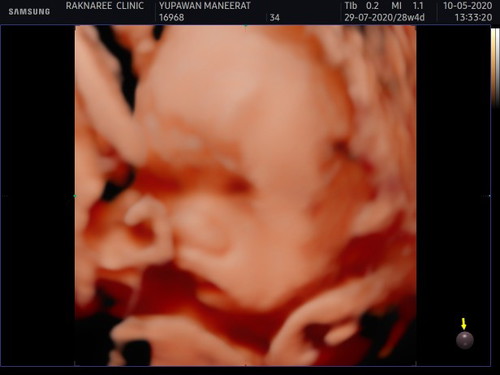

พอดีท้องเราท้องที่2แล้ว แต่ท้องนี่คุณหมอบอกคลอดเองไม่ได้เพราะแม่มีภาวะ รกเกาะต่ำ ตอนนี้กังวลมากค่ะ ท้อง 32w น้องยังดิ้นเก่ง ถีบแรงอยู่เลยค่ะ คนแรกคลอดเอง คนที่2 นี่ต้องผ่าเลยกังวลนิดหน่อยนะ เพราะวันที่ 13 /6/63 หมอนัดซาวใหญ่อีกรอบเพื่อดูว่ารกเกาะแน่นไหม ถ้าเกาะแน่นจะเป็นเคสใหญ่ แม่ๆท่านไหนเคยเป็นไหมค่ะ ??? มีรูปตัวเล็กมาให้ชม น้องตัวใหญ่เกินเกณฑ์ด้วยค่ะ ???